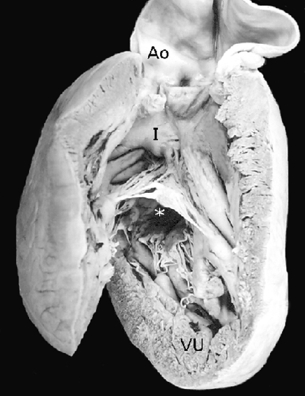

Los 2 corazones formaron parte de un situs solitus auricular, ambos con doble entrada a ventrículo único a través de una válvula auriculoventricular común cuyas valvas estuvieron adosadas a la pared ventricular; las grandes arterias normalmente relacionadas emergieron del ventrículo único con estenosis pulmonar infundibular y valvular (Fig. 5); el adosamiento y desplazamiento valvares cubrieron toda la porción de entrada y la zona trabecular posterior hasta la región apical con una gran auricularización del ventrículo único; estuvieron ausentes las cuerdas tendinosas y los músculos papilares (Fig. 6); la porción funcional efectiva del ventrículo se redujo a la zona trabecular anterior y a la región infundibular (Fig. 5). En el segundo corazón las grandes arterias estuvieron también normalmente relacionadas pero con dilatación y ambas emergieron del ventrículo único (Fig. 7). El adosamiento y desplazamiento valvares estuvieron reducidos a la porción proximal de la válvula por lo que la auricularización fue menor y mayor la porción funcional del ventrículo único (Fig. 8). Ambos corazones tuvieron un tabique interauricular pequeño con foramen primum (Tabla 1).

Figura 5 Vista externa anterior de un corazón en situs solitus auricular con doble entrada en ventrículo único y anomalía de Ebstein de la válvula auriculoventricular común. Las grandes arterias están normalmente relacionadas y emergen del ventrículo único. Obsérvese la porción funcional del ventrículo único ubicada en la zona trabecular anterior y en las zonas subinfundibular e infundibular. AD: aurícula derecha; Ao: aorta; AI: aurícula izquierda; AP: arteria pulmonar; VU: ventrículo único.